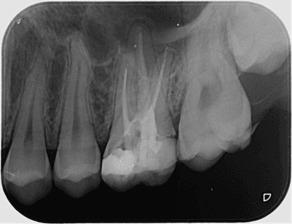

Секторни зъбни снимки

Зъбни снимки

Това са най-разпространените зъбни снимки. За да имат добра диагностична стойност, те трябва да обхващат целия зъб - коронката, корена и прилежащата около него кост. Така лекарите по дентална медицина могат да констатират наличието на много заболявания като кариеси, грануломи, кисти, пародонтални проблеми, както и да проследяват развитието на кореново лечение или интеграцията на поставените импланти.